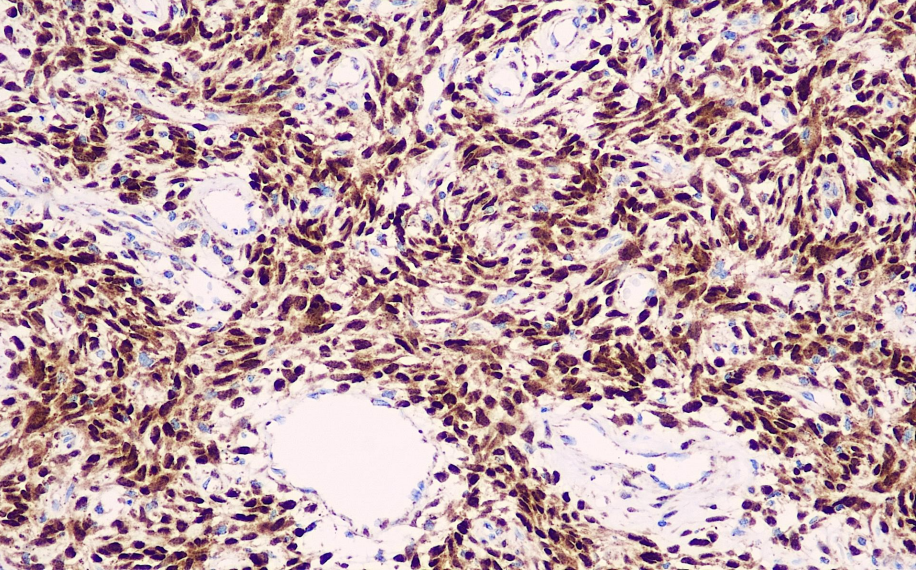

Positive control: Isolated fibrous tumor

Signal Transducer and Activator of Transcription 6 (STAT6) is a transcription factor responsible for mediating IL-4 immune signaling in the Jak/STAT signaling pathway. STAT6 has recently been identified as a reliable reference biomarker for distinguishing solitary fibrous tumors from other soft tissue tumors. Gene fusions are commonly observed in solitary fibrous tumors. Recent next-generation sequencing studies have demonstrated that the NAB2-STAT6 fusion is formed by the reverse fusion of two adjacent genes on chromosome 12q13 in 55–100% of isolated fibromatous tumors. However, due to the difficulty in detecting this fusion via FISH, further analysis is challenging. ISFT is classically characterized by CD34-positive spindle cells; however, approximately 5–10% of these tumors are CD34-negative, posing challenges for research. Cheah et al. used a rabbit monoclonal antibody against STAT6 for immunohistochemical (IHC) staining in 54 cases of SFT, and the results showed that all SFTs were positive, indicating that STAT6 exhibits high sensitivity and specificity in SFT expression.

STAT6 antibody reagents can specifically bind to STAT6 molecular antigens. Immunohistochemistry kits containing STAT6 antibody reagents are suitable for the precise diagnosis of solitary fibrous tumors (SFT).